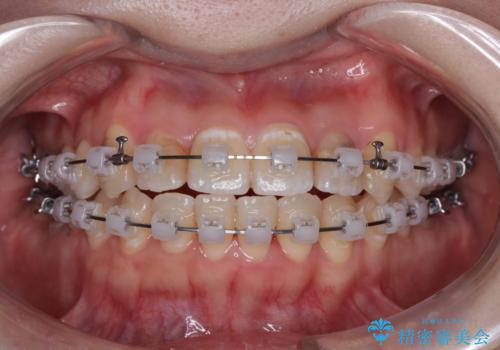

- 矯正装置

- クリアブラケット

急速拡大が奏効し、非抜歯矯正にて八重歯を解決することができました。

矯正治療後半で結婚式を挙げられたそうですが、参列された方々からは綺麗に整った前歯に大変驚かれたそうで、非常に満足されていらっしゃいました。